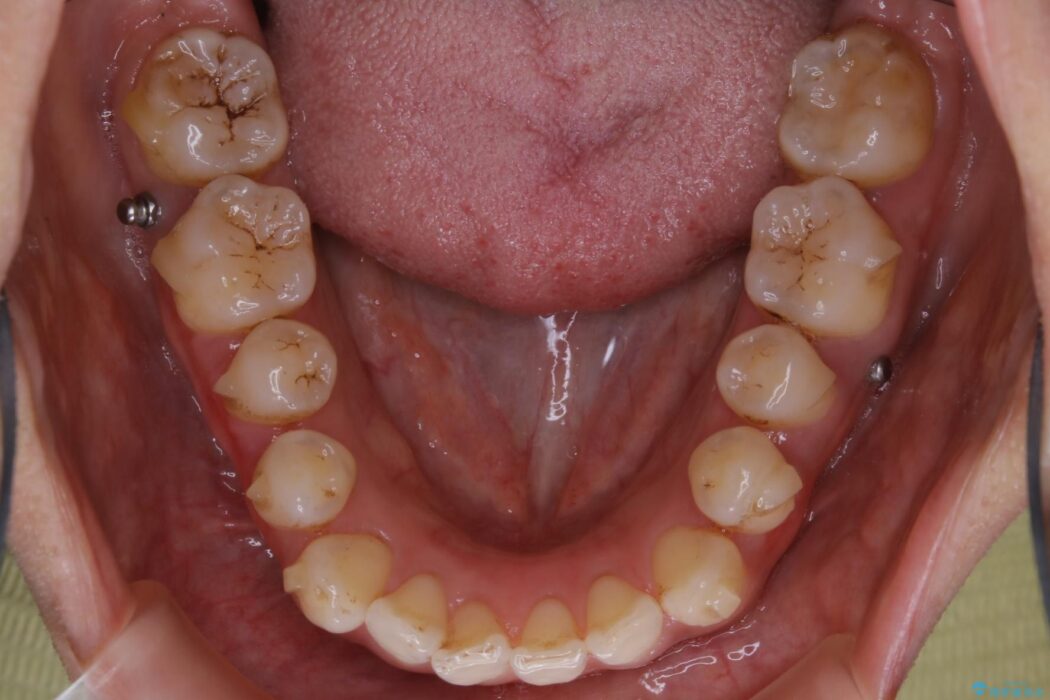

開咬により上下の噛み合わせが悪く、歯列の凸凹も合わせて治療したいとのことで来院されました。

なるべく非抜歯にて治療をするためインビザライン(マウスピース)とマイクロインプラントを併用した治療を行いました。

マウスピースとマイクロインプラントの併用により矯正するための隙間を確保し、治療期間は長くなりますが非抜歯できれいな歯列弓を得ることができます。